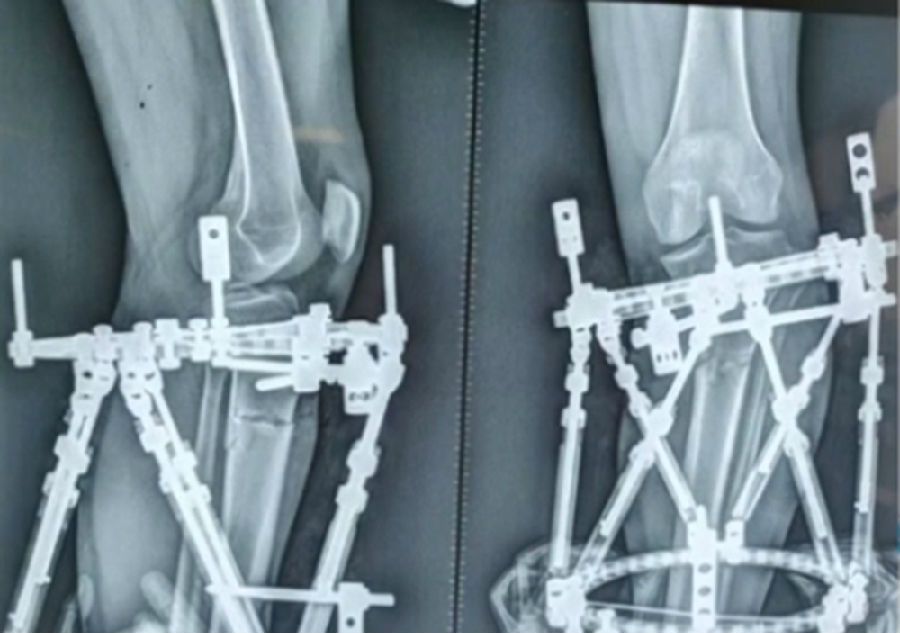

典型病例,女性,35岁,农民,左膝内翻、短缩、内旋。

术前

泰勒外固定架缓慢矫正短缩、内翻、前弓、内旋。

术中

该患者截骨后,做MAD矫正,目标MAD=0。患者术后1个月即达到设计的效果。

术后1个月